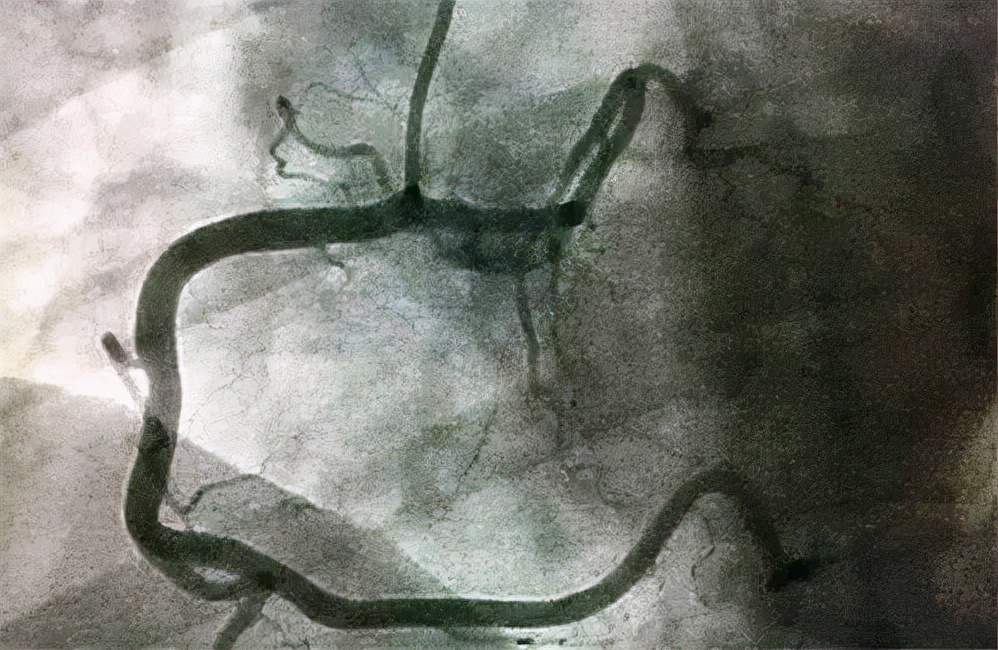

冠脉造影作为诊断冠心病的依据,用一根直径小于2毫米的软管,通过动脉的穿刺进入冠状动脉区,向冠状动脉骨内注入一定的造影剂。让冠状动脉的形状和细节在X光线下投射到电子屏幕上。

冠脉造影可以让医生辨别出患者的心脏内部是否有狭窄,X光线投射到电子屏幕上的图像可以让医生更加明确的看到血管的狭窄位置,不同地区的狭窄程度以及狭窄程度是否严重,还能够通过图像判断出患者的血管是否存在着严重的痉挛和畸形。

(冠心病)